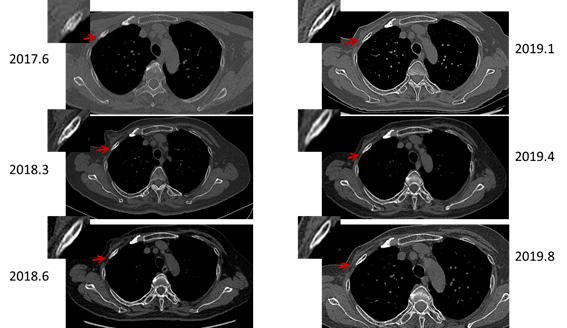

看如何决策:乳腺癌伴右上肺结节及两下肺病变_手机搜狐网